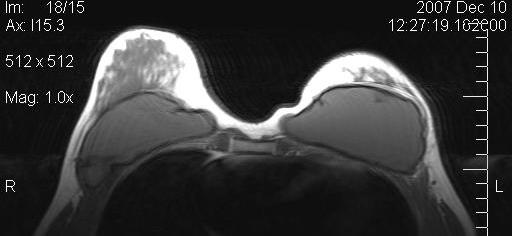

Figure 10 [Fig. 10] and Figure 11 [Fig. 11] show the MRIs of a patient pre- and postoperatively.

Figure 10: Preoperative MRI of a patient with capsular contracture

Figure 11: Postoperative MRI of the same patient after implant removal and subsequent fat grafting